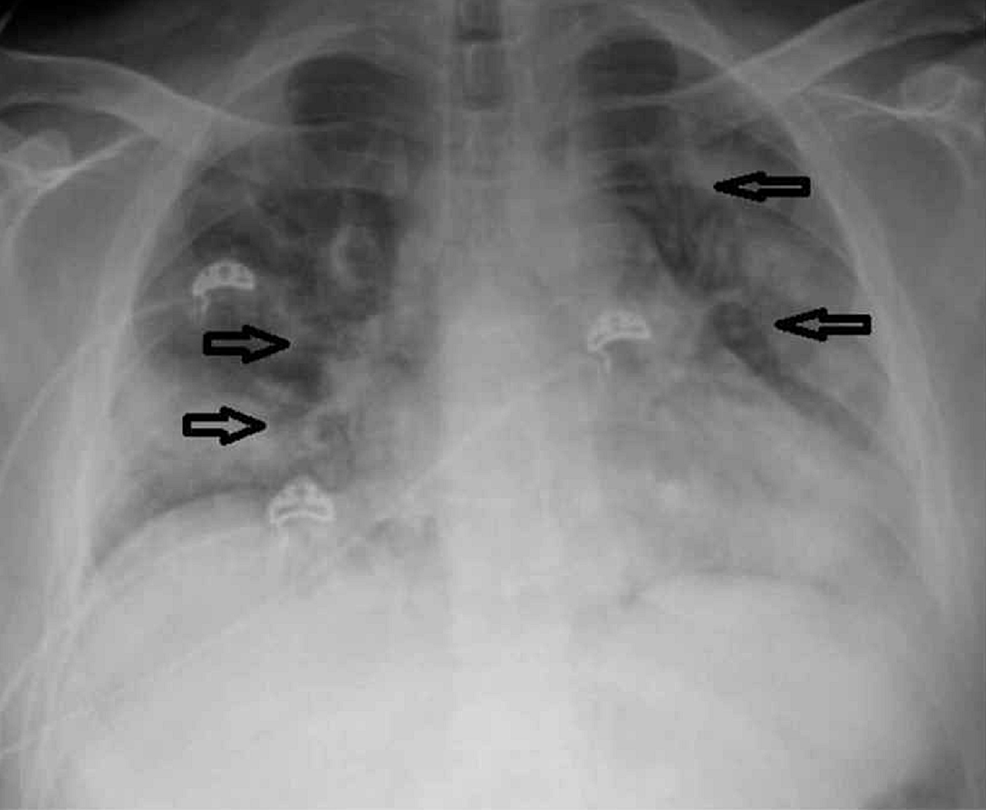

The chest X-ray revealed cardiomegaly with bilateral lung infiltrates (Figure 1). Computed tomography (CT) of the chest without contrast revealed prominent multifocal pneumonia and multiple ground-glass airspace opacities throughout all lung fields (Figure 2).

The patient was started on treatment with hydroxychloroquine, azithromycin, and ceftriaxone for suspected COVID-19 and pneumonia. Electrocardiogram (EKG) was done every 48 hours to monitor the QTc interval. All EKGs showed a normal QTc interval (Figures 3-5). The MMF, prednisone, and lisinopril were held, tacrolimus was continued at a home dose, and the patient was started on methylprednisolone 50 mg every eight hours. Tacrolimus was stopped within 72 hours, as the patient continued febrile and hypotensive. The patient was started on norepinephrine for hypotension and required continued escalation of treatment with three pressors.